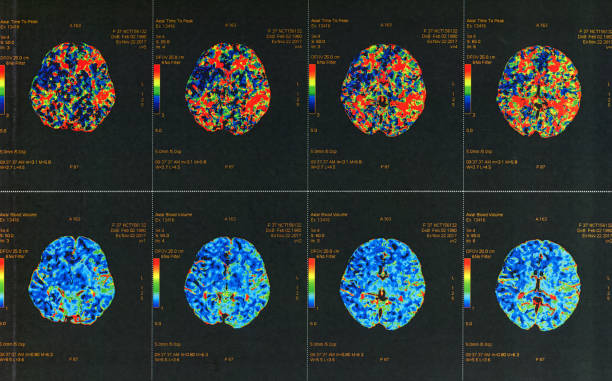

뇌출혈이 발생하면 다양한 증상이 나타날 수 있습니다. 이러한 증상 중에서도 특히 편측 마비, 말 능력의 손실, 의식 변화 등이 나타날 경우 뇌출혈의 가능성을 고려해야 합니다. 이런 경우 즉시 의료기관을 찾아 진단 받아야 합니다.